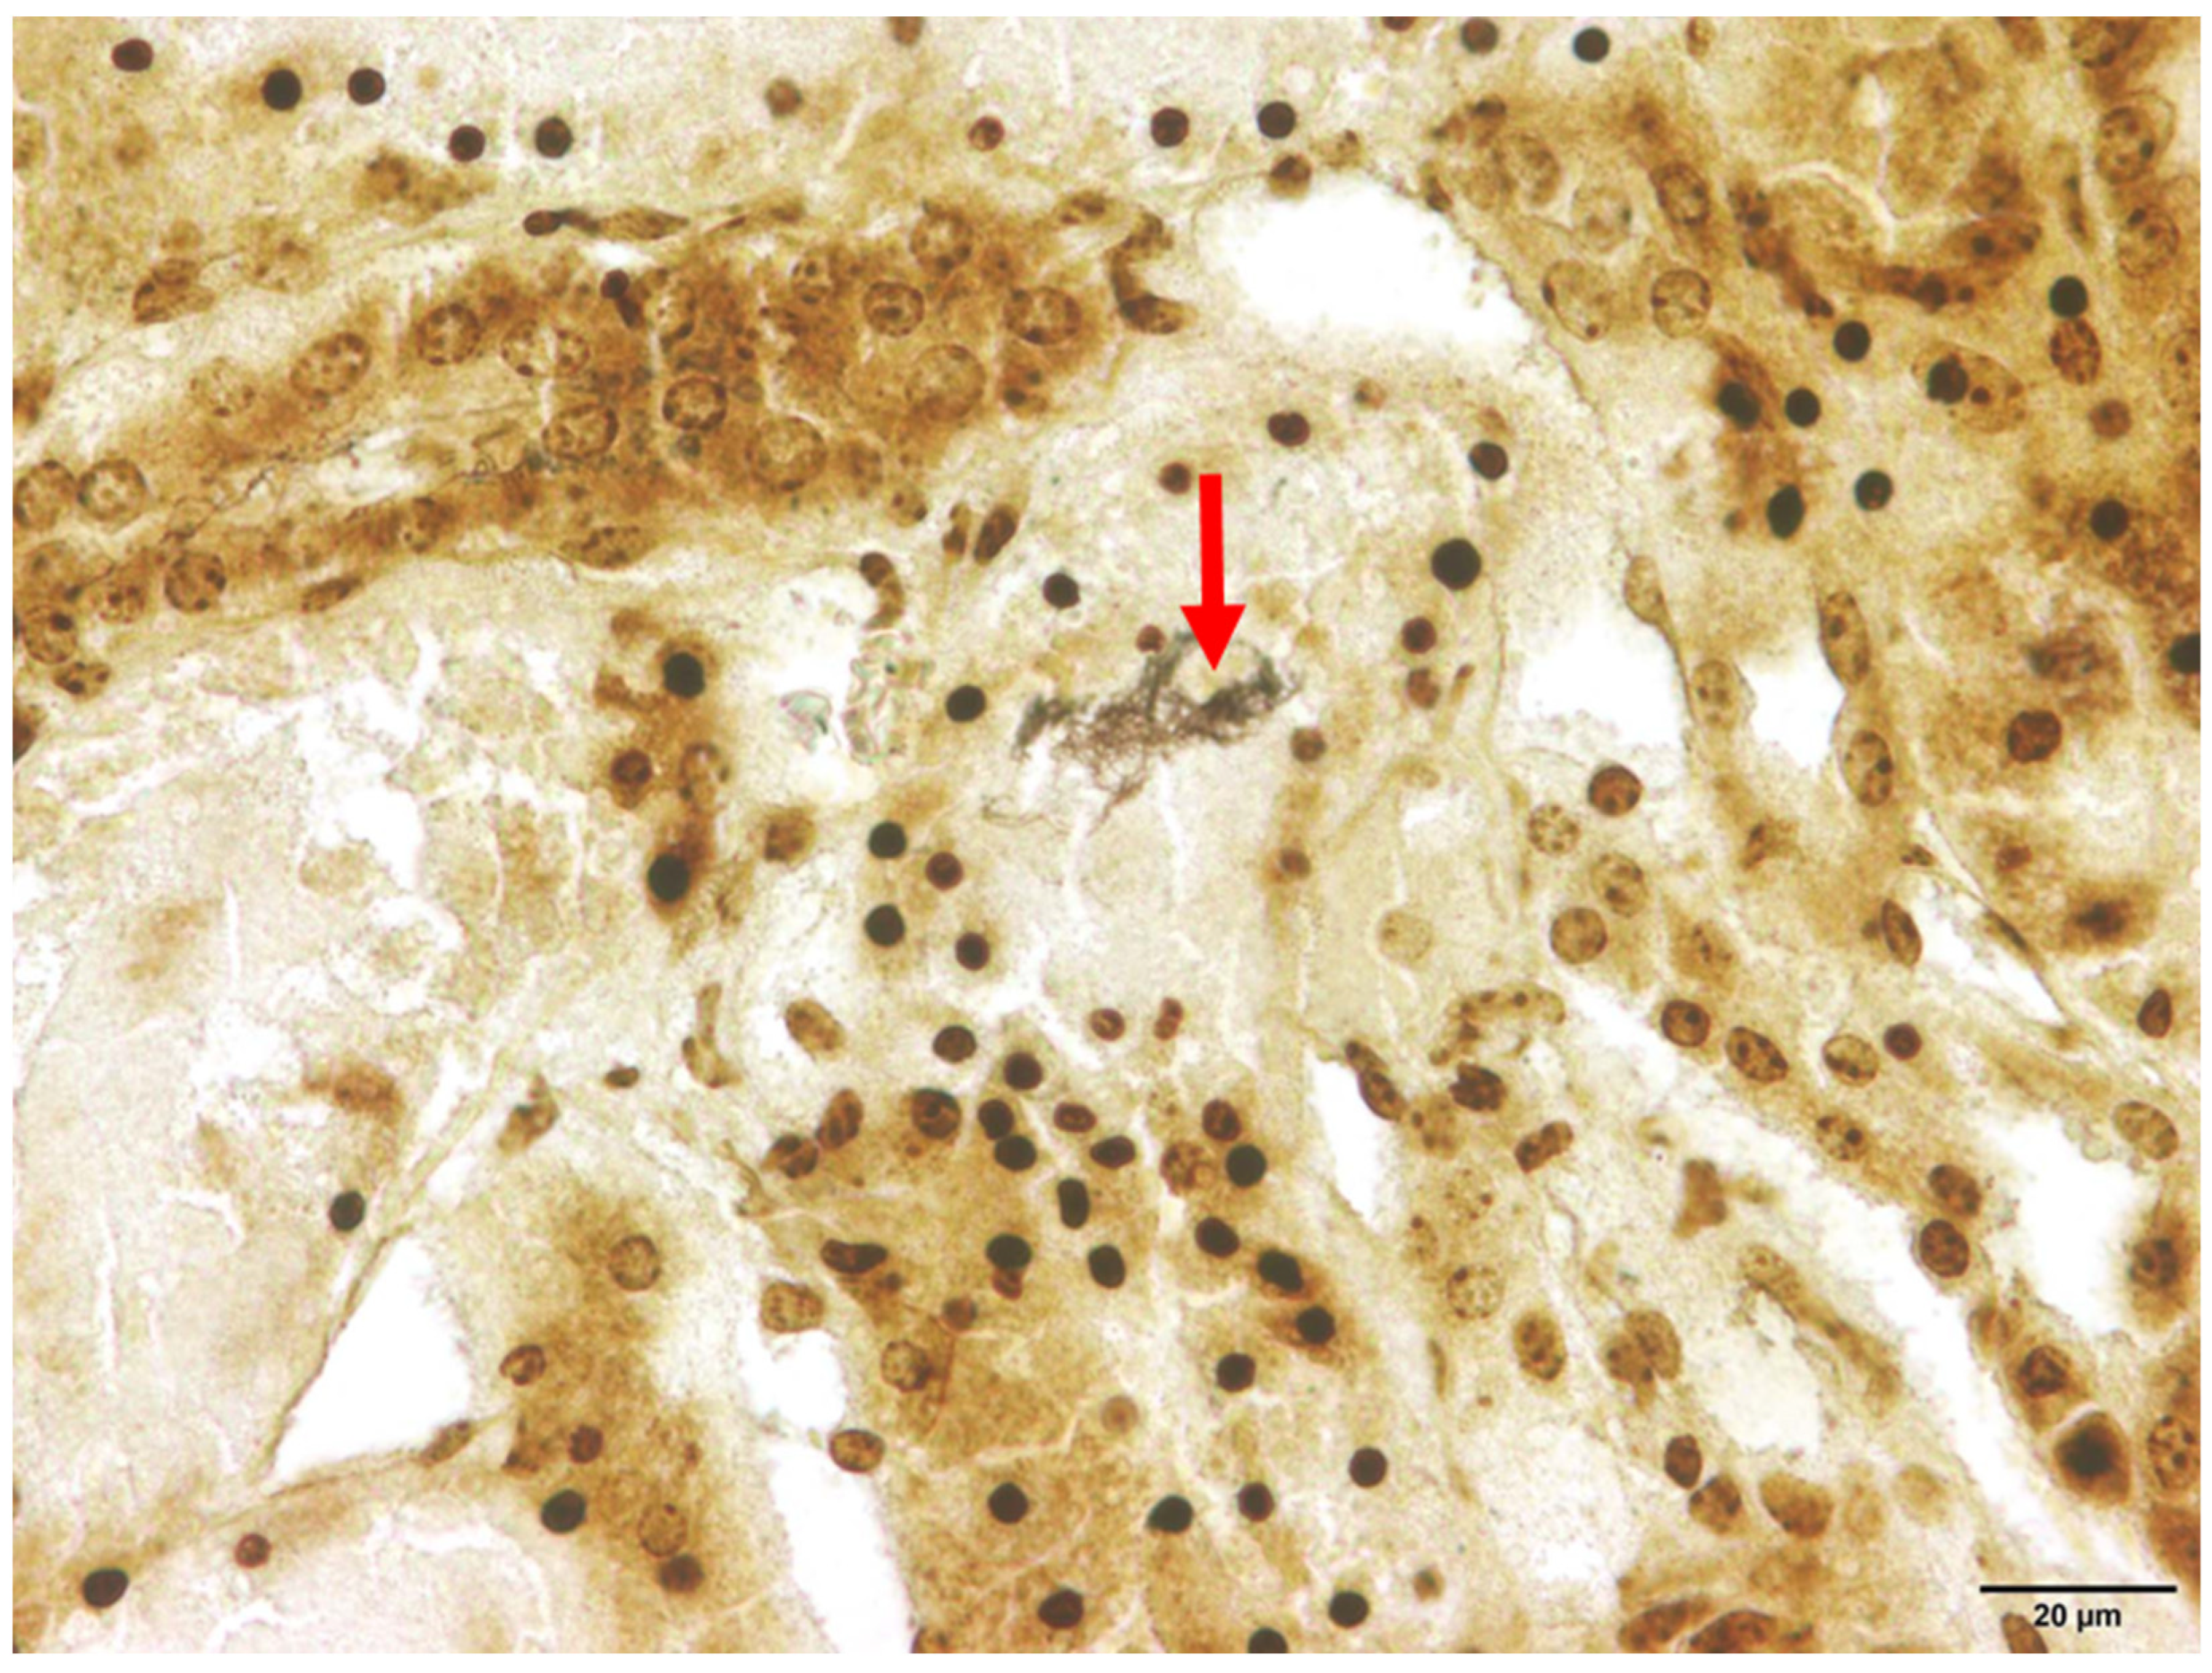

Among the animals that tested positive for Leptospira spp., interstitial nephritis was found in two raccoon dogs (2/21) and both raccoons (2/2). Therefore, interstitial nephritis was present in 9.5% of the affected raccoon dogs and in all raccoons. In none of the investigated animals histologic lesions attributable to acute and severe leptospirosis were detected, which, apart from focal to diffuse interstitial nephritis, includes acute transient tubular injury or tubular epithelial necrosis [61]. Using Warthin–Starry silver staining, spiral-shaped bacteria, corresponding to Leptospira spp., were successfully demonstrated within the renal tubules in one animal (Figure 3).

Figure 3.

Renal histology of a Leptospira spp.-positive raccoon dog (Nyctereutes procyonoides). Within the cytoplasm of the renal tubular epithelium, numerous spiral-shaped bacteria corresponding to Leptospira spp. (marked with arrow) are present. Warthin–Starry silver stain.